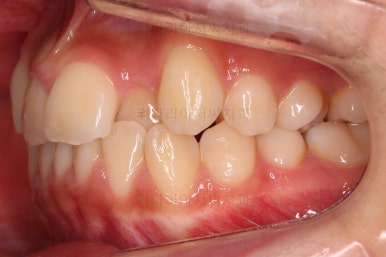

연산동치과 초진 시, 입안의 모습입니다.

보시다시피 앞니쪽이 많이 삐뚤고요. 어금니쪽이 긴밀하지 못한 부정교합이 있네요.

그리고 왼쪽 하단의 사진에 화살표를 보시면, 예전에 신경치료를 해둔 치아인데 어린 나이에 신경치료를 하다보니 크라운으로 치료를 마무리 하지 못했어요.